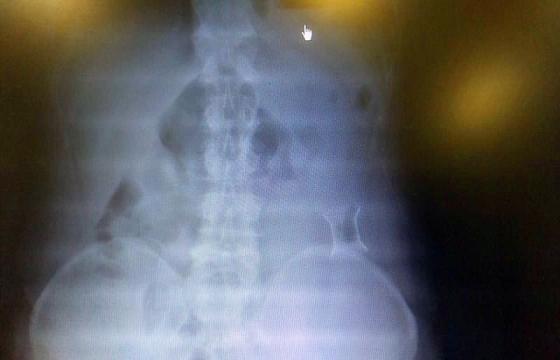

受試患者在結(jié)腸端端吻合術(shù)中,使用我司新研制產(chǎn)品達(dá)到了理想的預(yù)期效果?;颊咝g(shù)后7天、14天X光片顯影,可降解腸道支架均能按研制設(shè)計(jì)的預(yù)期時(shí)間節(jié)點(diǎn)保持應(yīng)有強(qiáng)度,術(shù)后21天X光片顯示可降解腸道支架已完全破碎,并排出體外。在整個(gè)試驗(yàn)過程中,病患無任何不良反映,耐受良好。